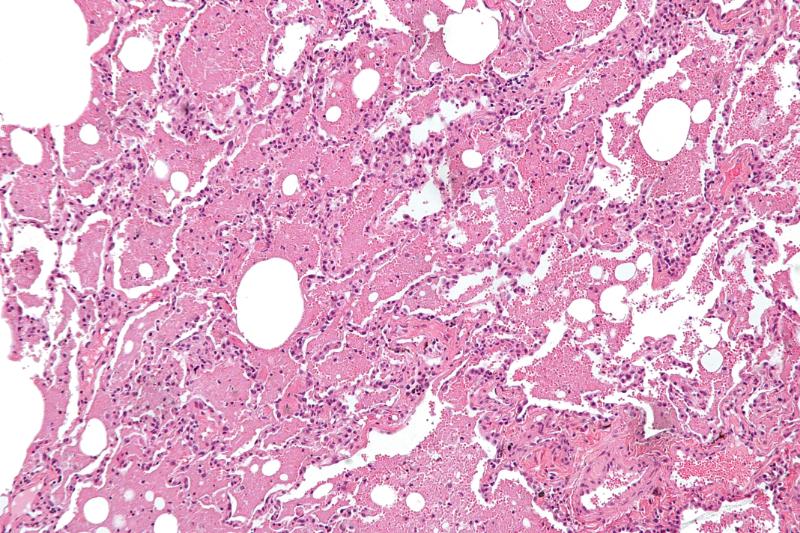

Формирование обструкции и эмфиземоподобных изменений

Постоянное воспаление приводит к ремоделированию дыхательных путей: утолщению стенок бронхов, гиперплазии слизистых желез, увеличению выработки слизи и сужению просвета бронхиол. Развивается стойкая бронхиальная обструкция, которая уже не является полностью обратимой. Повреждение альвеолярных стенок и межальвеолярных перегородок под действием воспалительных медиаторов и ферментов приводит к разрушению легочной паренхимы и формированию эмфиземы — расширению воздушных пространств дистальнее терминальных бронхиол с деструкцией их стенок. Эти изменения необратимо снижают способность легких к газообмену.

Особенности поражения легких при длительном воздействии биссиноза

Длительное игнорирование симптомов и продолжение работы в условиях воздействия текстильной пыли приводит к хронизации процесса. Легкие становятся менее эластичными, снижается их вентиляционная способность. Это состояние постепенно трансформируется в хроническую обструктивную болезнь легких (ХОБЛ), имеющую профессиональную этиологию. Ухудшается переносимость физических нагрузок, усиливается одышка, нарастают признаки дыхательной недостаточности. На поздних стадиях биссиноза изменения в легких становятся необратимыми, значительно влияя на качество жизни и продолжительность жизни пациентов.